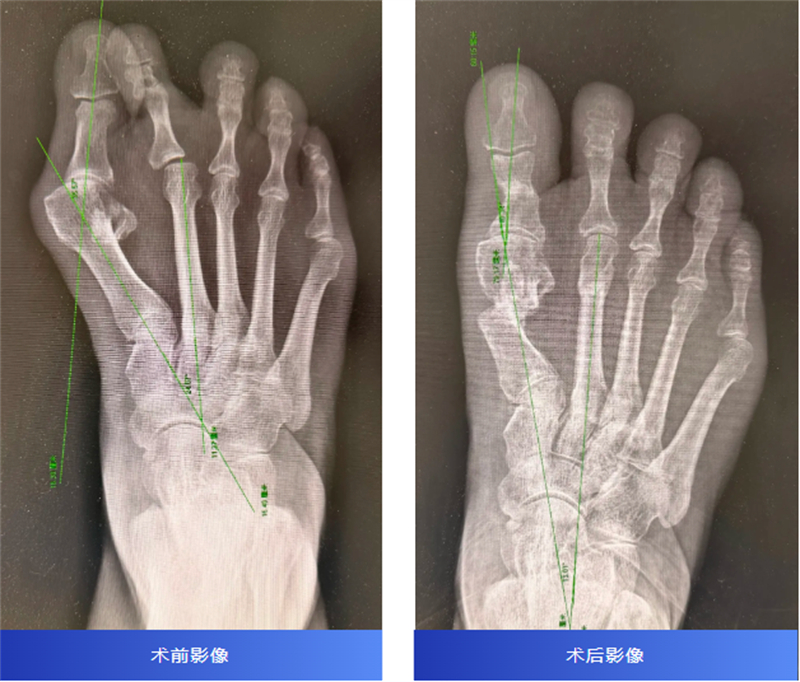

近日,一位飽受拇外翻困擾三十余年的王阿姨,在柳州市人民醫院運動醫學科接受了第四代MICA微創拇外翻矯形術,術后三個月復查時,她終于可以輕松穿鞋、自如行走,甚至重新跳起了心愛的廣場舞。

手術由韋釗嵐主任醫師團隊實施,與傳統開放手術不同,第四代MICA微創技術通過4個約3毫米的微小切口完成截骨與矯形固定,整個過程約一小時順利完成。

術后三個月復查X片顯示,截骨處已骨性愈合,足部外形得到改善,疼痛消失。韋釗嵐醫師鼓勵她:“可以逐漸恢復跑步和跳舞了!”聽到這個消息,王阿姨激動不已。